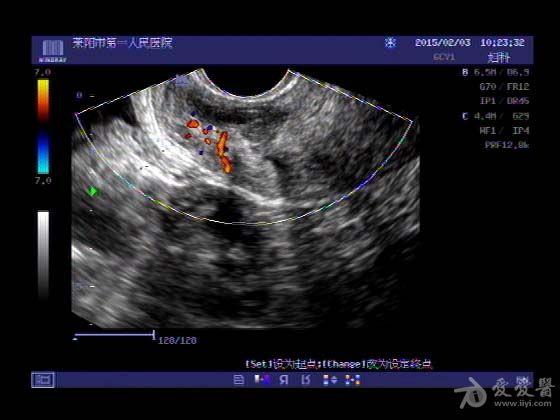

阴超子宫,阴超图子宫

医院要下班改做了阴超,请问子宫外的这个暗影区是什么

刚刚检查阴超,发现有一小颗子宫肌瘤,会不会影响胎儿?

子宫_阴超_子宫腺肌症_医疗健康_医疗健康

超声入门贴418--------宫颈癌(阴超图 病理图)

阴超图子宫

阴超宫外孕

阴超

子宫

子宫附件

阴超检查

阴超图解

阴超怀孕

子宫怀孕

子宫体

子宫后位

阴超设备

子宫位置

阴超男孩

阴超孕囊

阴超仪器

子宫肌瘤

阴超工具

阴超探头

阴超图片

子宫脱出

子宫结构

子宫解剖

子宫图片

子宫韧带

阴超检查怎么做

阴超报告单

阴超是如何检查的

阴超检查图片